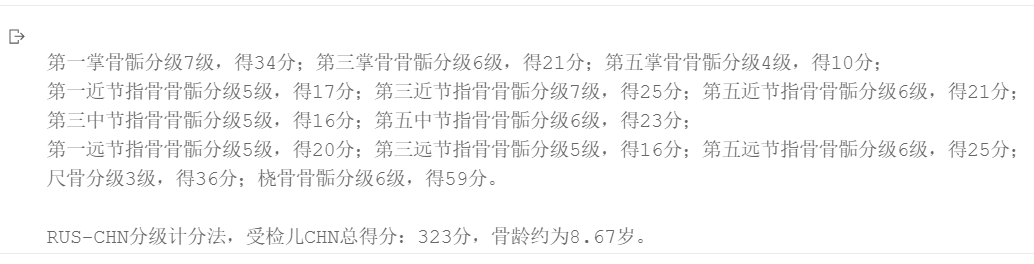

骨龄2